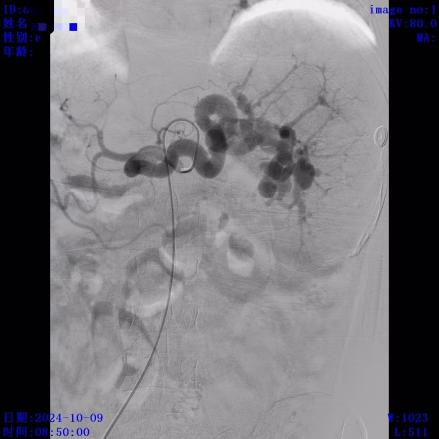

患者经内镜止血术后出血停止,返回病房继续对症治疗。术后复查患者血常规提示血红蛋白与术前相比有所回升,但血小板持续低下,最低达25(10^9/L),考虑与脾大、脾功能亢进(简称脾亢)有关。血小板是人体负责止血的血细胞,重度血小板低下会导致皮肤/牙龈出血、伤口渗血不止甚至严重内脏出血,严重影响生命健康,但脾亢常规药物保守治疗效果不明显,且血小板寿命短,输注血小板也仅仅能短期维持,非长久之计。结合临床,患者有行部分脾动脉栓塞术(PSE)以减轻脾亢指征。经患者及家属签字同意,10月9日由消化内科介入团队为患者施行经皮脾动脉部分栓塞术,过程顺利。术后经消化内科医护团队精心治疗,患者日前已顺利出院。出院后随访至今患者病情稳定,恢复良好,复查血常规提示血小板升至 72(10^9/L)。

脾血管造影

脾栓塞前

脾栓塞后